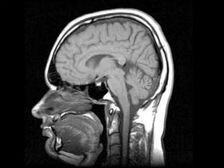

Fotografija iz odprtih virov

Novosibirski znanstveniki so razvili zdravilo, ki izdeluje človeški možgani za proizvodnjo matičnih celic, potrebnih za okrevanje obolelih organov. “Zdravilo se nanaša na regenerativno in nima analogov na svetu. Začenjamo letos klinična preskušanja, predklinična preskušanja, ki smo jih zaključili, “- je dejal predsednik uprave in solastnik podjetja, ki je razvil zdravilo, Andrei Artamonov. Po njegovem oz. zaradi drog možgani odraslih proizvajajo nove matičnih celic, ki kasneje najdejo poškodovan organ in obnoviti. “Pri otrocih možgani aktivno proizvajajo steblo celice, ker otrok raste. In možgani odrasle osebe sposoben jih je proizvesti, le tega noče storiti – njemu ni potrebe. Naše zdravilo spodbuja proizvodnjo lastnega stebla celic, “je pojasnil Artamonov. Po njegovih besedah so vse operacije s matične celice se zdaj proizvajajo zunaj človeškega telesa, ki nosi določeno tveganje, povezano z dejstvom, da lahko se prične spremenjena, umetno razmnožena celica komunicirajo na nepričakovanem mestu. Celice se lahko vnesejo, vendar to vedno tveganje, ker ni zelo jasno, kje so razlikovati. Čeprav so vaši, se razmnožujejo zunaj vašega organizem. Lastne matične celice tam ne morejo odpovedati razlikovati. Najdejo poškodovan organ in to začnejo obnoviti telo, “je dodal Artamonov. Klinična preskušanja droga bo trajala leto in pol, poroča Interfax.